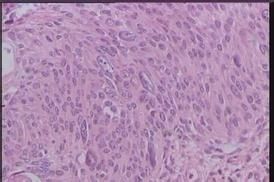

病理學檢查:可見腫瘤部位上皮細胞呈一致性增生,棘細胞為圓形或卵圓形,大小不一有明顯的極性紊亂和細胞核分裂像。在增生的上皮與正常上皮之間境界分明,腫瘤細胞局限於上皮內而不突破基底膜。完整而清晰的基底膜是本病與鱗形上皮細胞癌的主要鑑別之點。另一重要特徵是有奇異核的腫瘤細胞,核大而濃密與正常細胞相比,癌細胞的胞核占據整個細胞的極大比例,胞質較少。也可呈現為幾個核聚集在一起的多核瘤巨細胞,這種多形性巨核或多核細胞,可出現在上皮的各個水平。

腫瘤所在的上皮下有淋巴細胞浸潤和新生血管有些增生的腫瘤細胞,有明顯核仁,胞質呈伊紅染色新生血管多。腫瘤的表層有角化不全細胞但可見完整的前彈力膜。